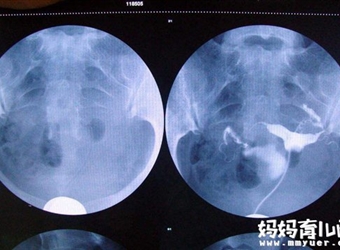

大家是否知道输卵尽管造影以后不能马上要孩子。这里给大家科普一下关于输卵管造影的的知识,包括输卵管造影后多久可以怀孕、输卵管造剂哪种最好、输卵管造影后…